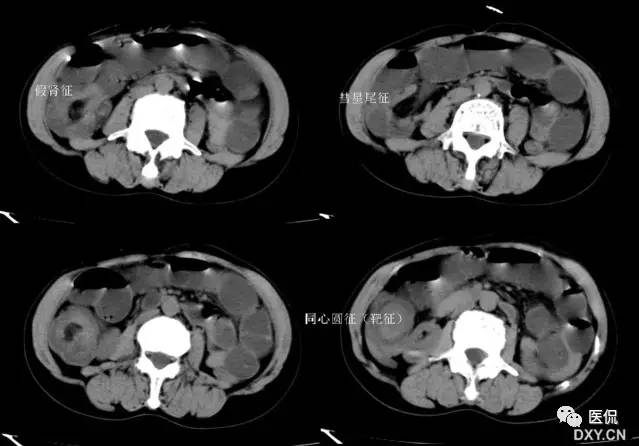

主要见于腹部增强扫描,增后的肠壁表现为三层结构,内层和外层是高密度强化层,两者之间是低密度的中间层。

靶征出现于可导致长鼻粘膜水肿、炎症或两者同时存在的多种肠管病变。其内层代表粘膜层,外层代表固有层和浆膜层,由于对比剂的强化而成高密度,中层的低密度被认为是由于粘膜下层水肿所致。靶征的出现提示粘膜和固有层、浆膜层的充血并伴有粘膜下水肿和炎症。颈静脉注射对比剂后,各层之间的密度差异在动脉早期和门晚期表现最为清楚,如果对比剂注入速度太慢、剂量太少以及延时超过2分钟,此征根本不出现。但是当粘膜下水肿非常严重时,CT平扫也可能出现。如果肠管内充满水而使肠管扩张时,靶征显示更为清楚。

CT扫描时,良性的肠管病变通常表现为肠壁的环形均匀性增厚,厚度从粘膜面到浆膜面一般不超过1公分,根据病因和病变严重程度的不同,偶尔可能超过1公分,但一般在2公分以内。肠壁出现靶征的病变主要见于缺血性肠病、小肠壁内出血、克隆氏病、溃疡性结肠炎、血管性疾病、感染性疾病、放射疾病和门脉高压所致肠粘膜水肿等。靶征并不是一个特异征象,但是在恶性病变中一般不出现此征,只是浸润性直肠癌是一个例外。

所以,一般情况下,靶征的出现,首先要考虑的是肠道的炎症性病变。以下病例是一个系统性红斑狼疮的年轻女性患者: